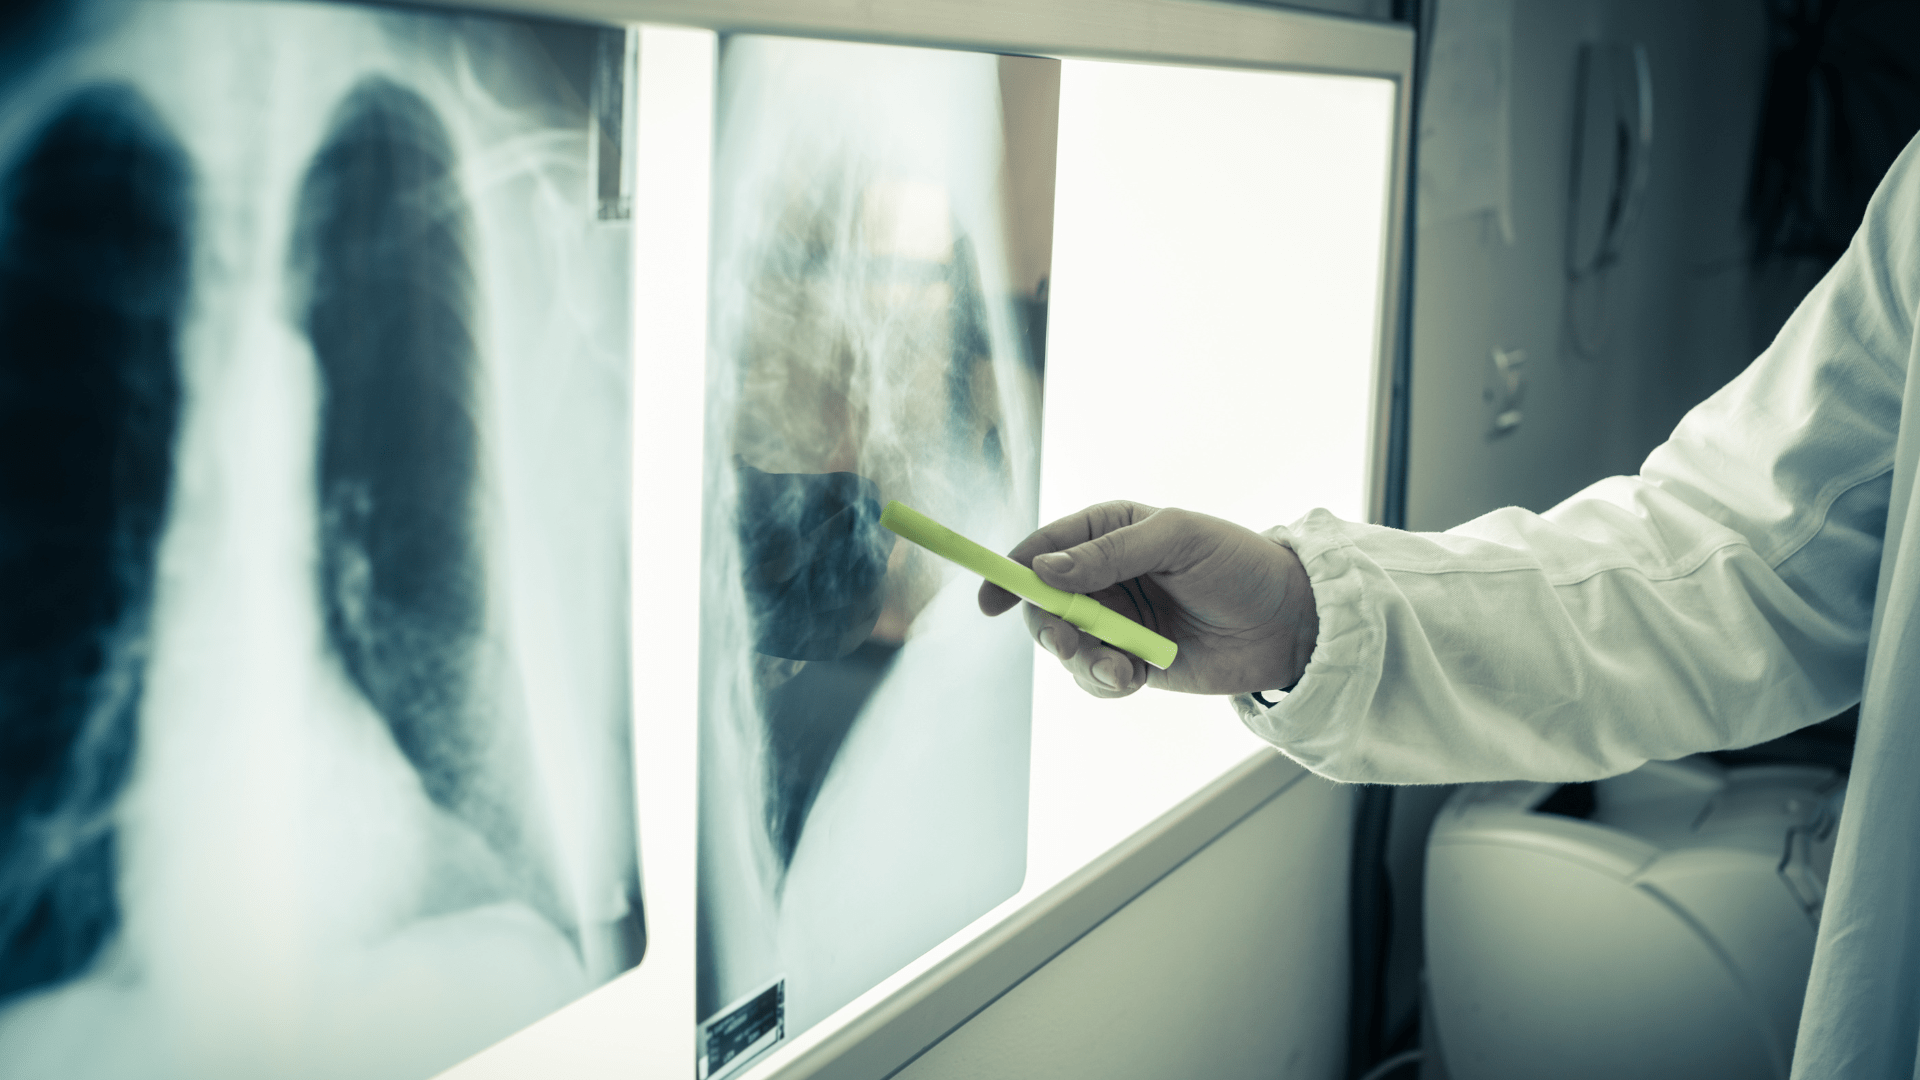

Dans le Parlons IA de la semaine 25, découvrez comment l’intelligence artificielle pourrait aider l’agriculture à devenir plus efficace et durable. Apprenez-en davantage sur les mises en garde de Mistral AI concernant le manque de centres de données et de capacités de formation en Europe. Explorez également comment les avancées de l’intelligence artificielle touchent désormais le domaine des soins de santé.